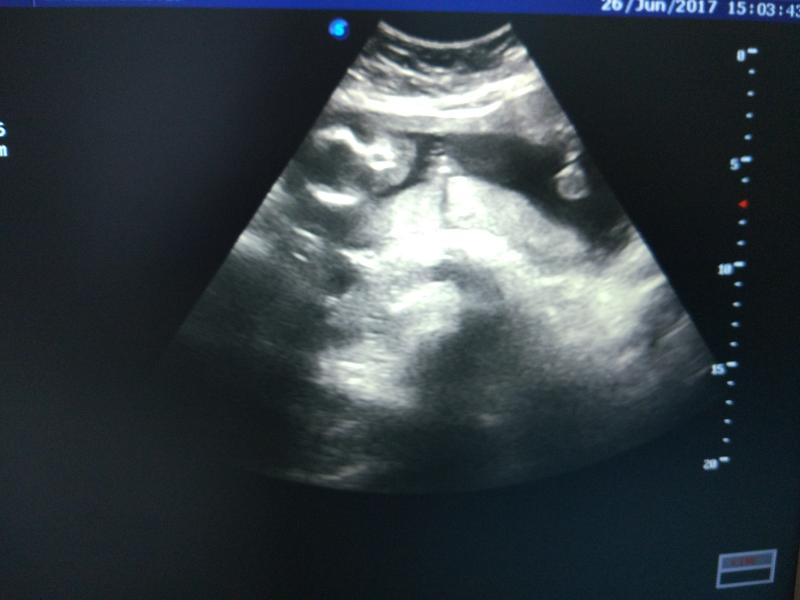

@nirvana_kabanova, ну если прям принципиально идти к кому-то на коммерческой основе, то почему бы и не к нему, согласна. Приятный врач и специалист наверное хороший. С другой стороны, есть ли острая необходимость в этом?.. что смотрят на третьем УЗИ? "Габариты" ребёнка😂, пол уточнят, как лежит (хотя это и так понятно уже на этом сроке) ну и доплером проверят кровоток и т.д... то есть, ничего особенного. Главное,чтобы не хамили))

Только сразу записывайтесь с уздг (кровоток смотреть) 3-й скрининг всегда с ним.